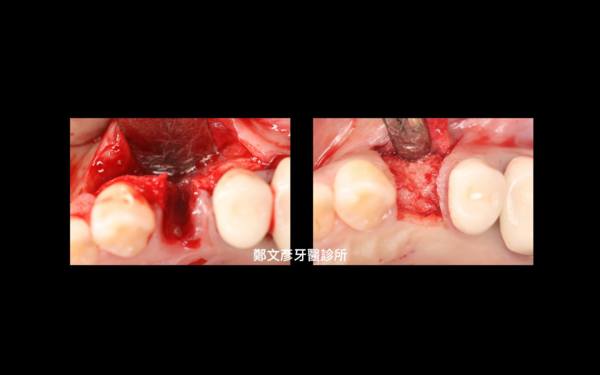

Role of granulation tissue in socket preservation

3. Role of granulation tissue in socket preservation